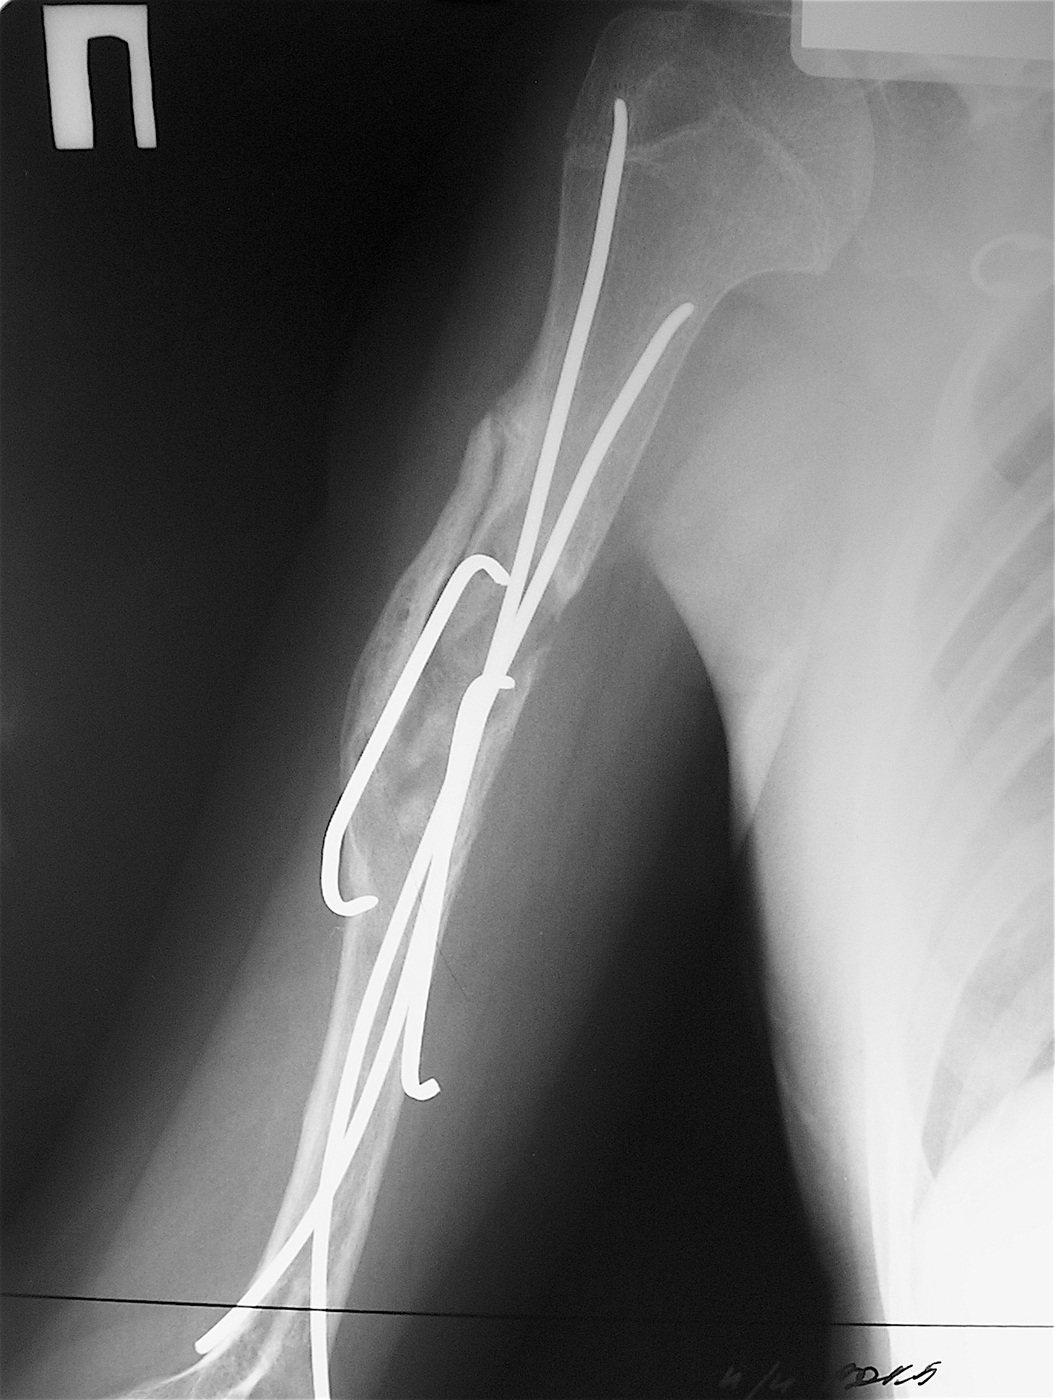

Закрытый, патологический перелом в с/з правой плечевой кости на фоне аневризмальной кисты диафиза правой плечевой кости.

Выполнена операция: экскохлеация кисты, остеосинтез титановыми эластичными стержнями и металлической скобой, аллопластика патологического очага материалом «Лиопласт».